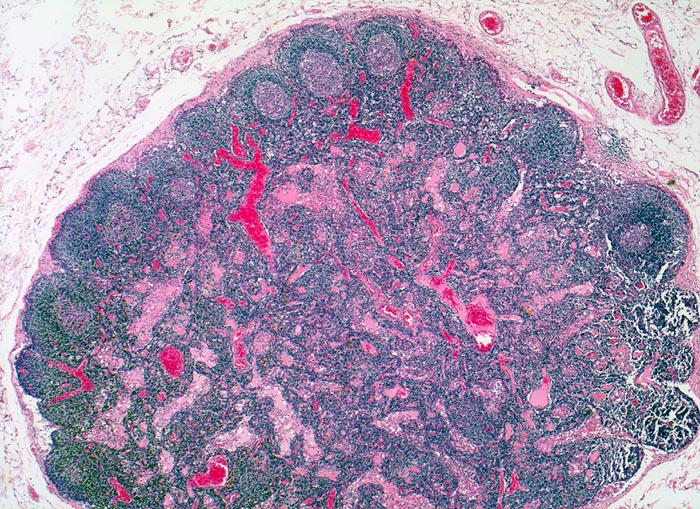

Lymphknoten Normalbefund

Lymphknoten, abdominal

Zarte Lymphknotenkapsel.

Normale Lymphknotenarchitektur mit Primär- und Sekundärfollikeln (mit Keimzentrum) in der Rinde. Im Zentrum des Lymphknotens das Mark mit zahlreichen Lymph- und Blutgefässen.

Lymphgefässe: Randsinus=Marginalsinus, Intermediärsinus, Marksinus.

Perikolischer tumorfreier Lymphknoten aus dem Abflussgebiet eines wenig fortgeschrittenen Kolonkarzinoms.

25

54